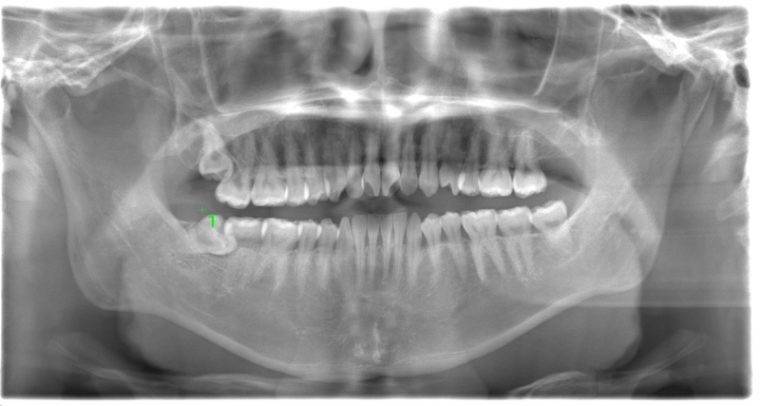

CASE 15

基本情報

| 年齢・性別 | 27歳・男性 |

| 主訴 | 左上の歯ぐきが痛い |

| 抜歯期間 | 30分 |

| 抜歯費用 | 約2,500円 別途CT撮影で3,000円 (2022年8月現在) |

| 抜歯内容 | 左上親知らずの半埋伏抜歯 |

| 治療方針 |

左上親知らずに数日前から痛みがあるとの事でした。親知らずと歯肉の間に細菌がたまり、歯肉が炎症していました。 レントゲンでは完全萌出してるように見えますが、実際は半分歯ぐきに覆われていました。今回は歯ぐきを切開して抜歯しました。 抜歯後はお痛みはなく会話もできて、いつも通りの生活を送れたとのことです。 |